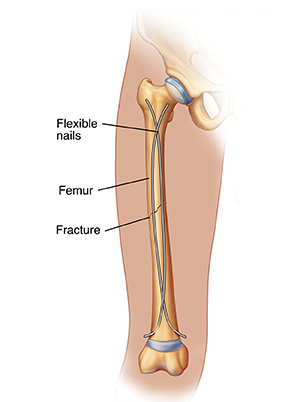

Understanding Femur Fracture Open Reduction and Internal Fixation (ORIF)

Open reduction and internal fixation (ORIF) puts the pieces of a broken bone back together so they can heal. Open reduction means the bones are put back in place during a surgery through a cut (incision). Internal fixation means that special hardware is used to hold the bone pieces together. This helps the bone heal correctly. The procedure is done by an orthopedic surgeon. This is a doctor with special training in treating bone, joint, and muscle problems.

| Flexible nails are one type of internal fixation. |

The femur is the long, thick bone in the upper part of your leg (thigh). Different kinds of injury, such as a car accident, sports injury, or fall, can cause the femur to break (fracture) into two or more pieces. In some cases, the bone may break but the pieces are still lined up correctly. Or, the pieces may not line up correctly. This is called a displaced fracture.

The surgery is done by an orthopedic surgeon. The surgery can be done in several ways. The surgeon will make a cut (incision) through the skin and muscles of your thigh. The surgeon puts the pieces of your femur back in place. This is the reduction. Then special screws, plates, wires, or pins are used to hold the bone pieces together. This is the fixation. A special metal rod may be put through the middle of the bone if you have a fracture in the middle of your femur. The rod screws into the bone at both ends.